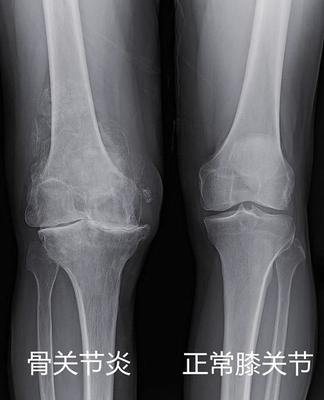

一张膝关节X光片,是膝关节炎的标准检查,也是最简单,最便宜,最有价值的。

如果x光片报告上告诉你,“退行性改变”、“骨赘形成”、“间隙变窄”、“髁间嵴变尖”、“软骨下骨硬化/囊变”,这些都是关节炎患者,常常出现的。